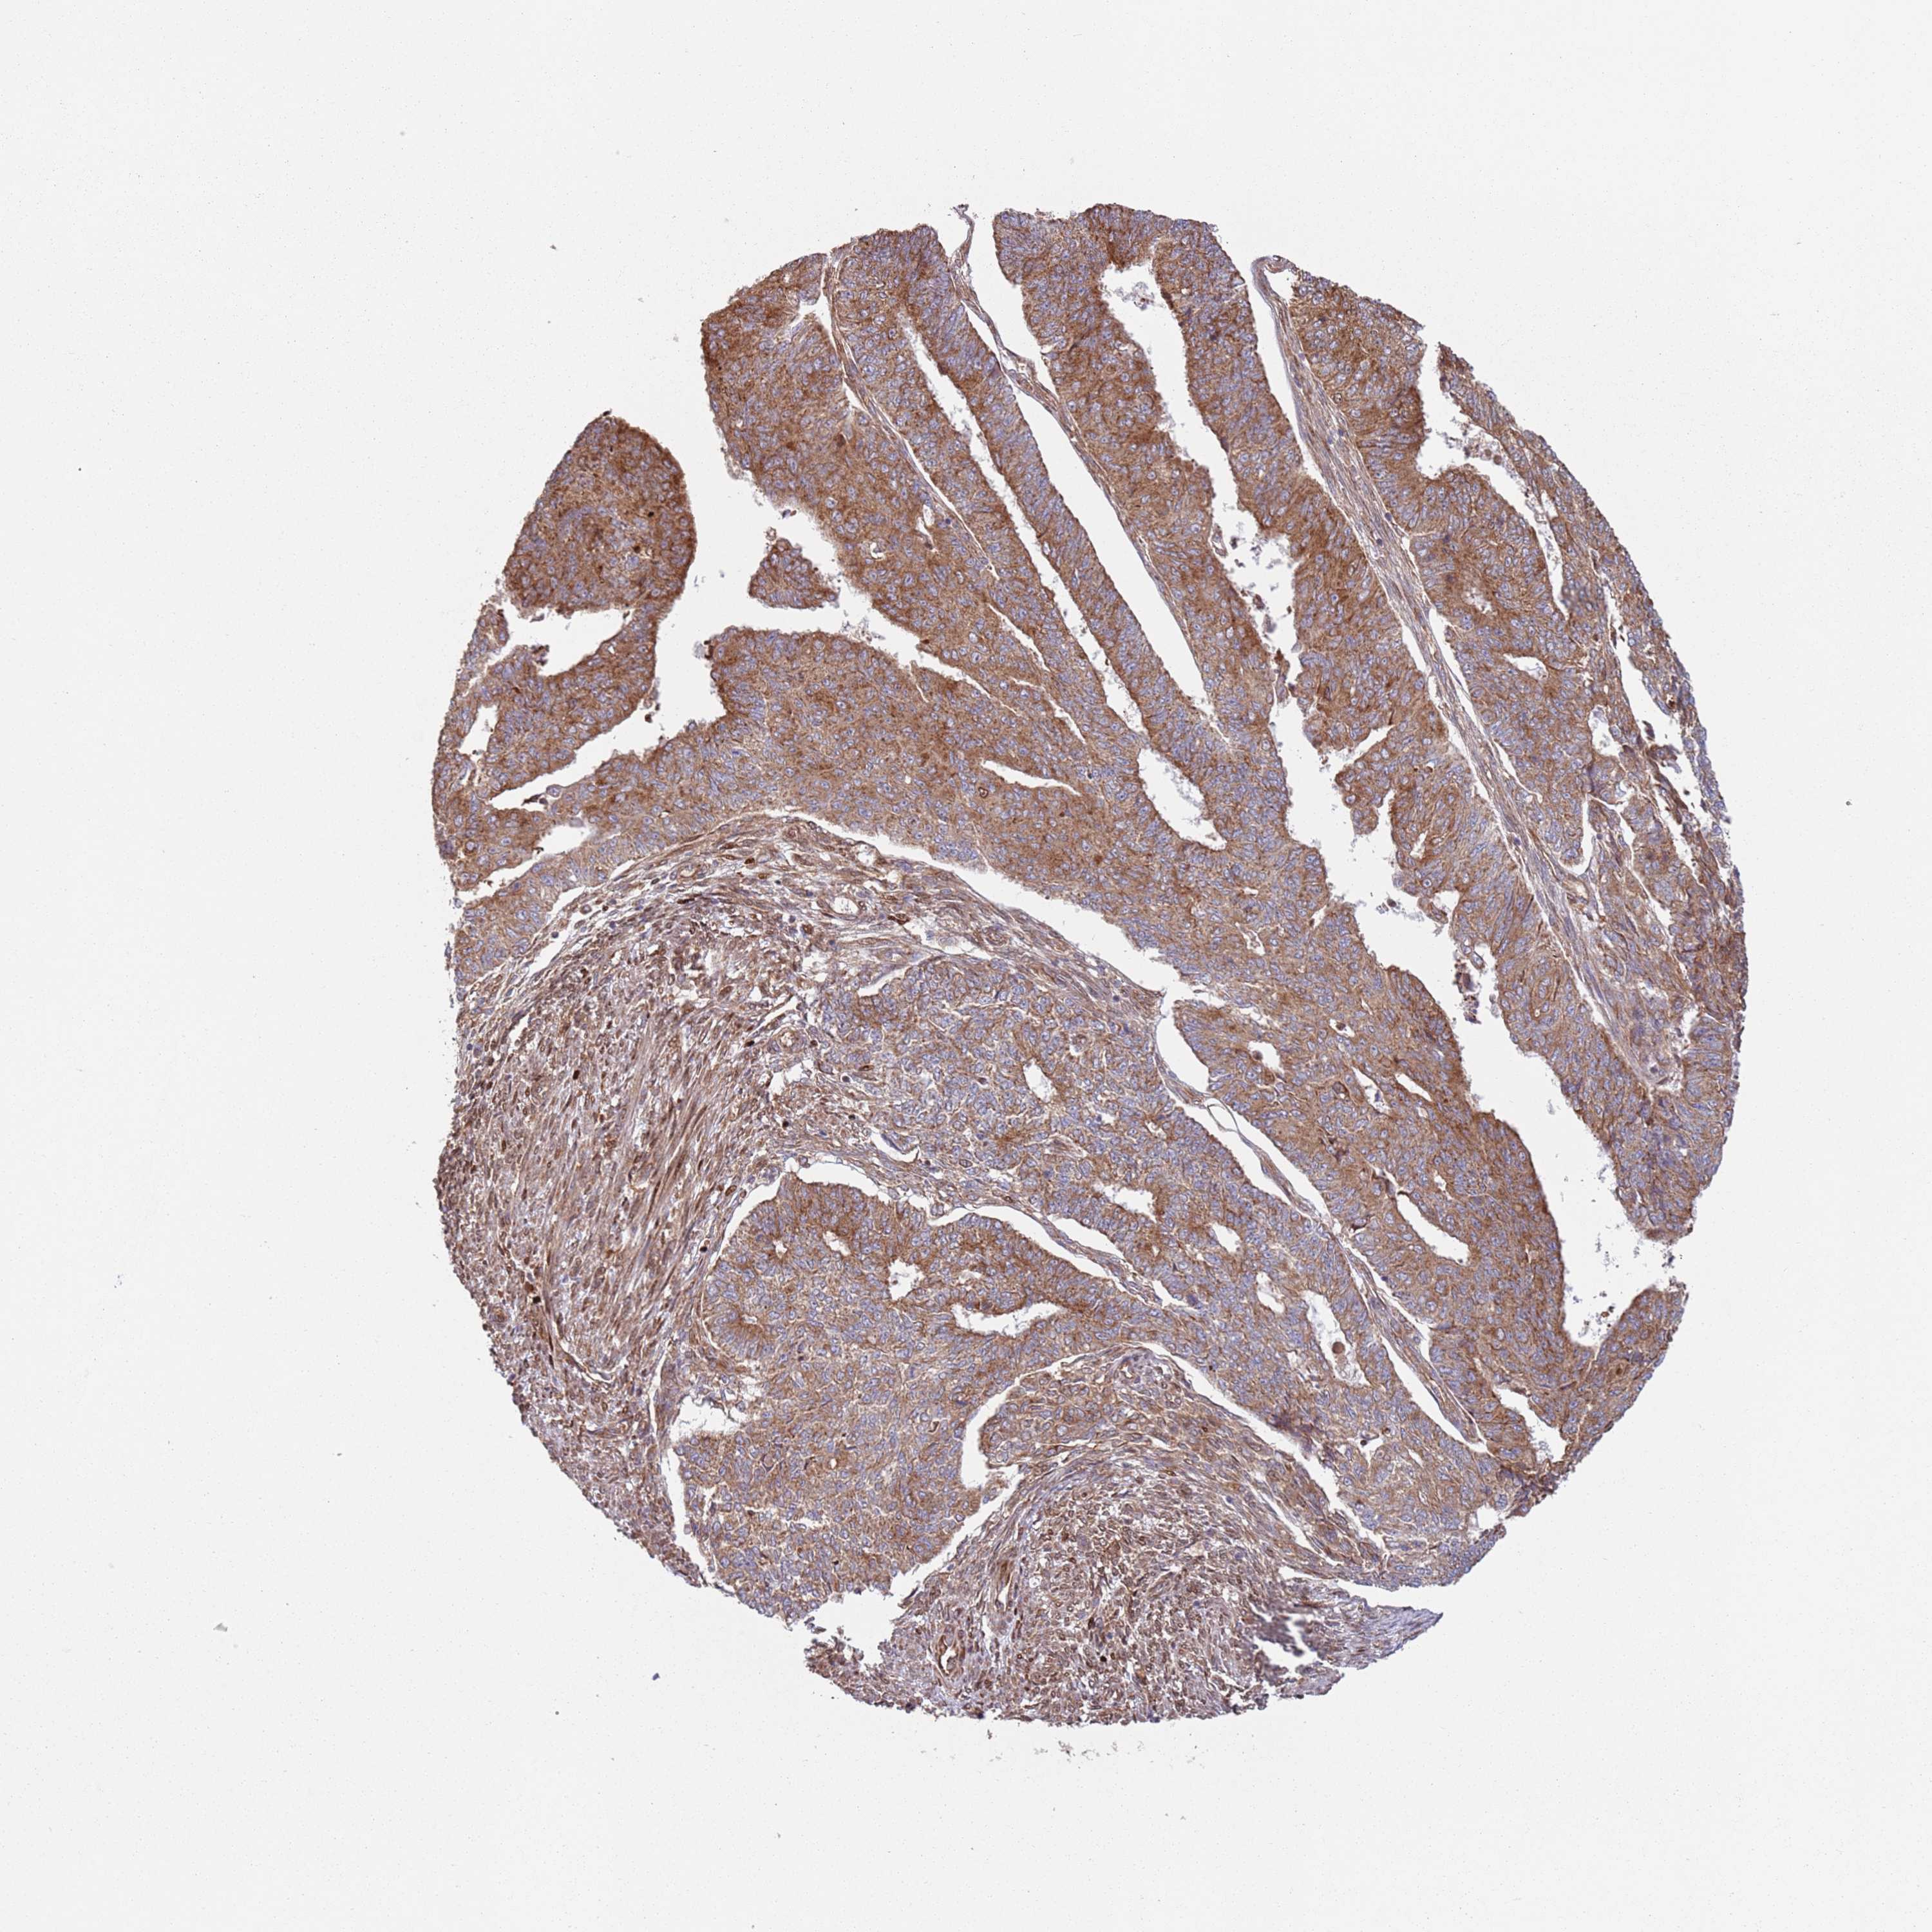

ENDOMETRIAL CANCER - Protein expressioni

A mouse-over function shows sample information and annotation data. Click on an image to view it in a full screen mode. Samples can be filtered based on level of antibody staining by selecting one or several of the following categories: high, medium, low and not detected. The assay and annotation is described here.

Note that samples used for immunohistochemistry by the Human Protein Atlas do not correspond to samples in the TCGA dataset.

Antibody stainingi

Antibody staining in the annotated cell types in the current human tissue is reported as not detected, low, medium, or high, based on conventional immunohistochemistry profiling in selected tissues. This score is based on the combination of the staining intensity and fraction of stained cells.

Each image is clickable and will lead to virtual microscopy that enables deeper exploration of all samples and also displays staining intensity scores, fraction scores and subcellular localization as well as patient and tissue information for each sample.

Antibody HPA046084

Staining

High

Medium

Low

Not detected

Intensity

Strong

Moderate

Weak

Negative

Quantity

>75%

75%-25%

<25%

None

Location

Nuclear

Cytoplasmic/membranous

Cytoplasmic/membranous,nuclear

Adenocarcinoma, NOS